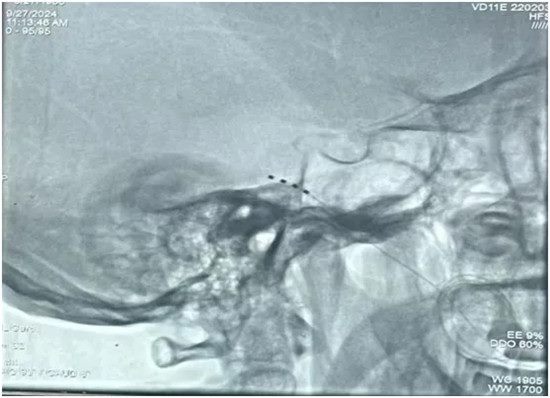

半月节电刺激术是一种通过向三叉神经半月节处发送微弱的电信号来缓解疼痛的技术。在这个过程中,一个小型的电刺激器被植入到疼痛覆盖区域,术中全程DSA引导精准植入电极(图1),通过导线与神经相连,电刺激器可以发送特定的电信号,从而缓解疼痛,并且在缓解疼痛的同时,并不损害患者的三叉神经的正常感觉和运动神经功能。患者在治疗过程中保持清醒状态以配合测试。测试成功后患者会带着临时刺激器回病房,接受7-14天左右的电刺激。术后医生会用体外程控仪对神经电刺激系统进行无创性的设置和调整,操作非常方便灵活。疼痛控制理想后将置入的刺激器取出,患者全程清醒无痛苦。

▲ 术中患者电极植入影像